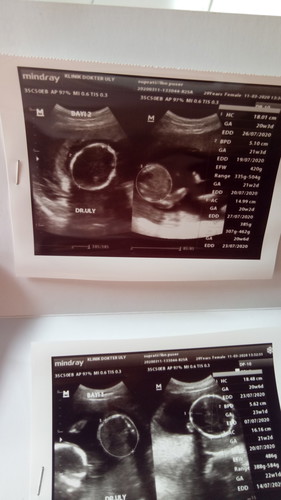

USG

Alhamdulliah hasil USG ku punya bayi kembar Padahal anak pertama